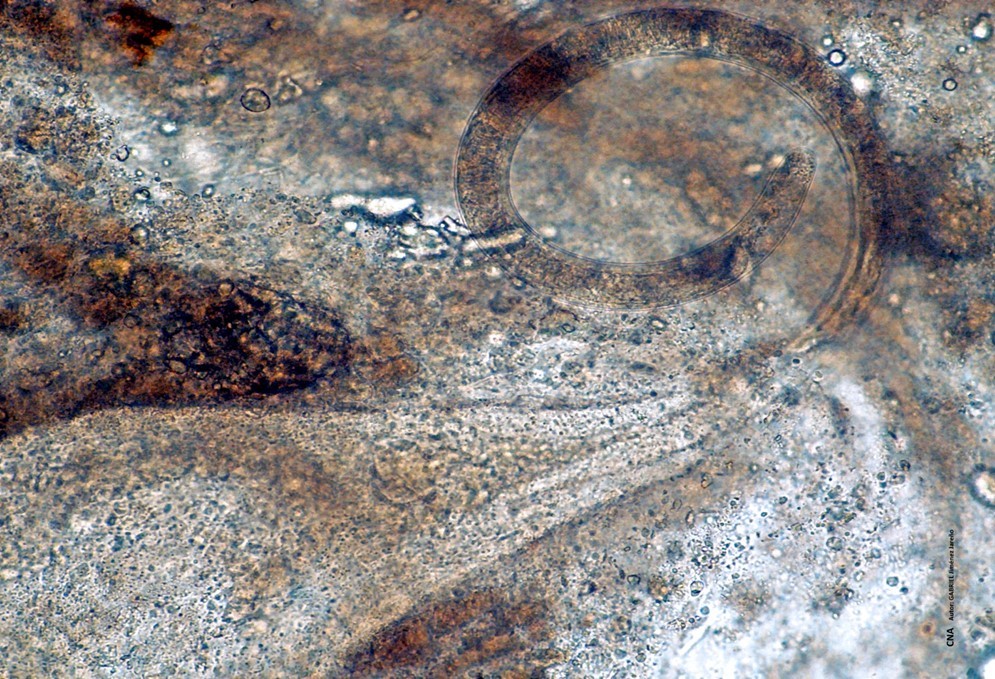

Fotomicrografía de quiste y larva parcialmente fuera del mismo de Trichinella spp. en fibras de tejido muscular